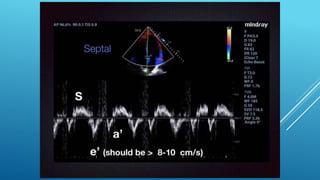

โ€ข Tricuspid annular systolic velocity

โ€ข Tissue Doppler of the free lateral wall

โ€ข An Sโ€™ value < 9.5 cm/s should raise the suspicion for abnormal RV function

โ€ข RIGHT VENTRICULAR โ€ขSIZE AND FUNCTION โ€ข ================= โ€ข Visual examination is the most commonly used method to quantify right ventricular function (RVF) โ€ข Tricuspid annular plane systolic excursion โ€ข TAPSE of <17 mm indicates RV dysfunction โ€ข Fractional area change (FAC) value of less than 35% indicates RV systolic dysfunction โ€ข Tricuspid annular systolic velocity โ€ข Tissue Doppler of the free lateral wall โ€ข An Sโ€™ value < 9.5 cm/s should raise the suspicion for abnormal RV function โ€ข Right ventricular hypertrophy is present if the free lateral wall of the RV exceeds 5 mm โ€ข RV End diastole diameter > 41 mm (base) and โ€ข > 35 mm (mid level)=RV dilatation โ€ข > 83 mm (longitudinal) = RV enlargement โ€ข free-wall strain of less than โˆ’20% (less meaning smaller absolute number) indicates reduced RVF. Mean values for RV strain in healthy controls are โˆ’29% ยฑ 4.5 โ€ข RV myocardial performance index (RIMP) and the rate of RV pressure rise during early systole (dP/dt) proved to correlate with pulmonary vascular resistance and to predict a reduced RVEF โ€ข โ€ข PSAX distal RVOT diameter is 27 mm โ€ข โ€ข PLAX proximal RVOT is 30mm โ€ข โ€ข PSAX proximal RVOT is 35mm